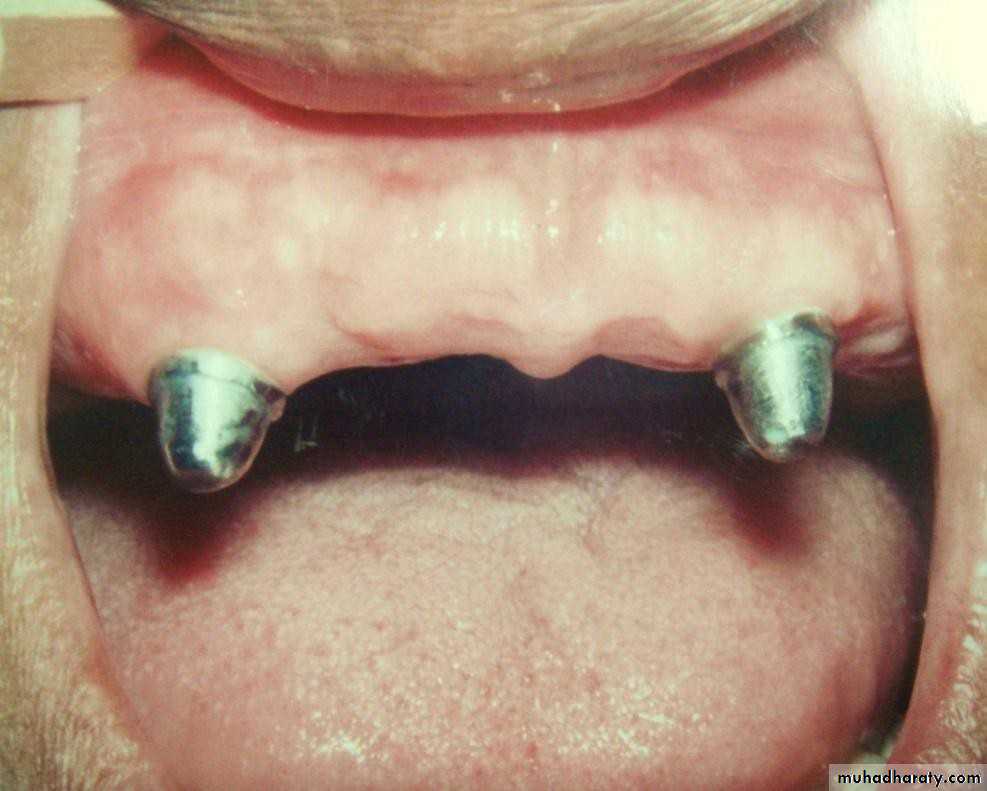

• 4) Short (1-2mm):

• a) conform to the curvature of the alveolar ridge (Dum-shape).• b) very low profile.

• c) indicated for max. favourable C/R

• ratio.

• d) can be used with the stud

• attachment.